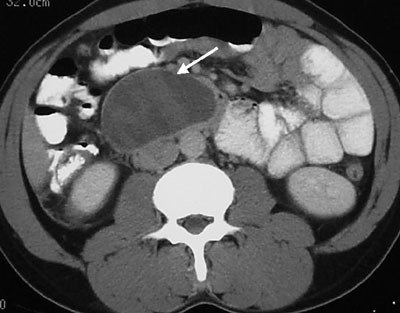

- Kontrastlı KT və ya MRT standart müayinədir, şişi və yayılma dərəcəsini müəyyənləşdirilməsində önəmlidir.

- Görüntüləmdə: erkən arterial fazada contrast tutan və venoz fazada yuyulan, MRT-də hipointens, ətraf toxumalara invaziv, böyüməyə meylli, baş nahiyyəsində yerləşərək xoledoxu və pankreatik axacağı genişləndirən (“iki axacaq simptomu”) törəmə

- Kontrastlı KT və ya MRT ilə pankreasda kütlə təyin İnsulinomalardan fərqli olaraq qlükaqonomalar böyük ölçülü olurlar və tapılması çətinlik törətmir. Adətən cisim və quyruq nahiyyəsində yerləşirlər.